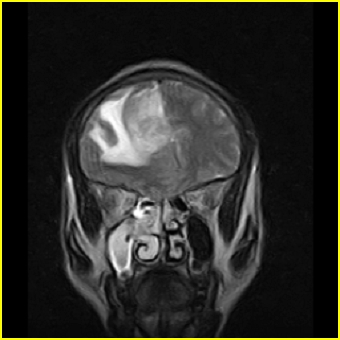

男,45岁,头部剧烈疼痛伴呕吐5天。

右侧额叶见较大的类圆形长t1信号环绕等t1环影,长t2信号环绕短等t2环,周围见明显水肿占位征,中线结构左移,男,45岁,头部剧烈疼痛伴呕吐5天。

病灶紧贴大脑镰,周围见有大片水肿,考虑:1.脑膜瘤伴水肿,2.胶质瘤。

右侧额叶,见一占位病灶,t1像病灶、水肿长t1;其间为短t1环行信号。t2像病灶、水肿长t2,其间为短t2环行信号。占位效应明显,中线左移,右测脑室受压闭塞。结合患者发病较急。首先考虑:右侧额叶脑脓肿形成。鉴别:1、转移瘤,多发多见2、胶质瘤。建议增强